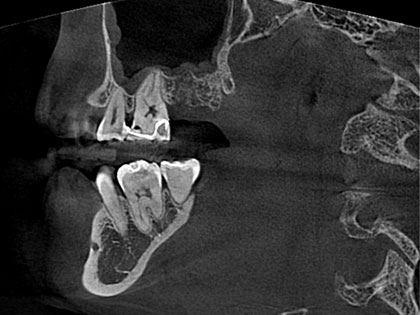

• インプラント術前2